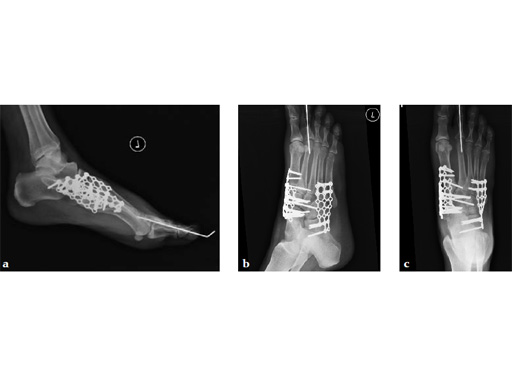

As isolated fusion of the talonavicular joint is often hard to achieve, a 4.0 mm lag screw a plus X-plate was used (see Fig. 2a-c).

Fusion of the talonavicular joint while saving the rest of the hindfoot complex motion was achieved (see Fig. 4a-c).

The patient was treated with arthrodesis of the talonavicular and subtalar joints. The compression/ distraction device was used to restore the length of the medial column. The articular surface of the subtalar joint was prepared arthroscopically. The talonavicular joint was debrided then packed with a tricalcium matrix. Length was maintained using a locking X-plate. The subtalar joint was then fixed with a 6.5 mm headless compression screw.

The patient returned to work 3 months after surgery. He wears an ankle brace when on uneven surfaces. His lateral column and subtalar pain have resolved.